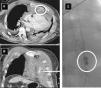

We hereby present the case of a sixty-six-year-old male admitted to the hospital to receive a double-J catheter for the management of his urinary lithiasis. Forty-eight hours after the procedure the patient suffers from an in-hospital cardiac arrest. On high suspicion of PTE an intra-cardiac arrest systemic thrombolysis is conducted; the resuscitation maneuvers go on for another 45min until spontaneous circulation is recovered. Afterwards, the patient suffers from a hemorrhagic shock as identified by the CT scan: fracture of the middle third of the sternum and the anterior side of several left ribs, and retrosternal active bleeding coming from the patient's left internal mammary artery (Fig. 1A and B). The arteriography confirmed such bleeding (Fig. 1C) and a selective embolization procedure was conducted with good results. The patient progressed satisfactorily.